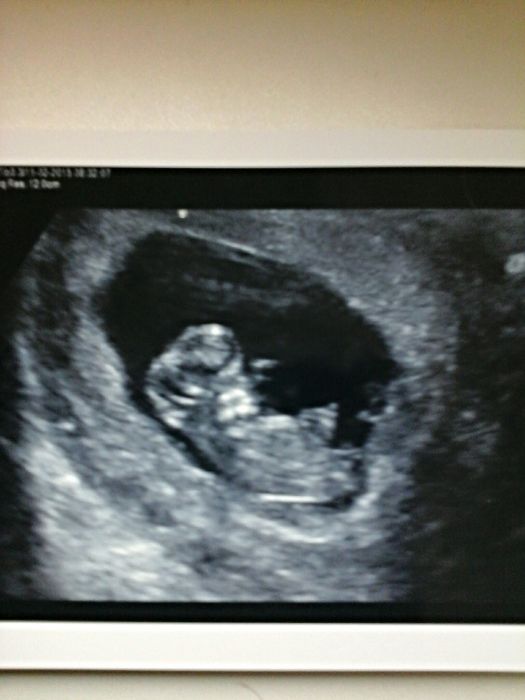

Ja byla na prvnim ultrazvuku 5+5tt a srdicko na už tlouklo, zitra ráno jdeme na další kontrolu. Dostanem fotku a průkazku. Tak snad bude vse v pořádku.

Tak na kontrole vse v poradku. Podle UZ uz 10+5. Za 14 dni na další kontrolu.

V pondělí to bude první poradna, UZV, krev.....snad i foto....tak jsem zvědavá

Já v to utery čekák taky, že bude krev a žádanka na genetiku. Snad i uzv a foto :-)

[701769] Lenys presne takhle jsem to mela ja dnes. Ultrazvuk, foto, pak krev a 14 dni pro výsledky a další ultrazvuk.